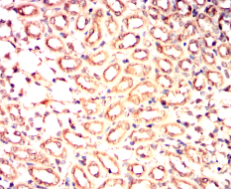

IHC    1/200 - 1/1000